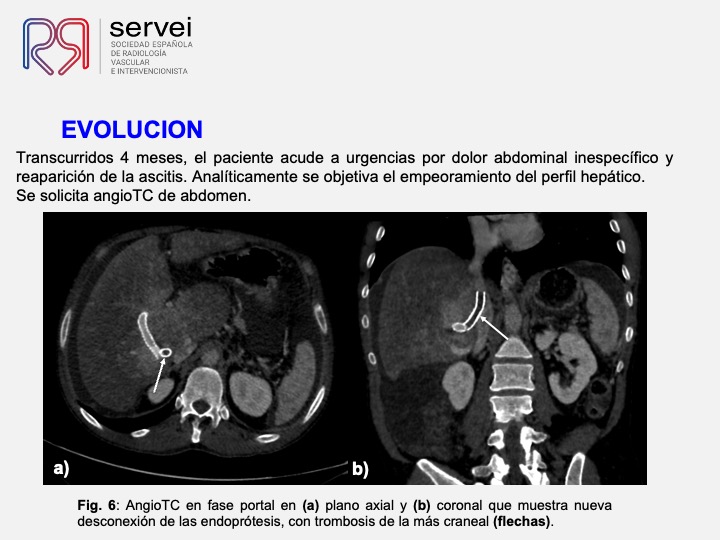

DIPS con técnica de “gun-sight”. Paciente con Síndrome de Budd-Chiari y eventual trombosis protésica